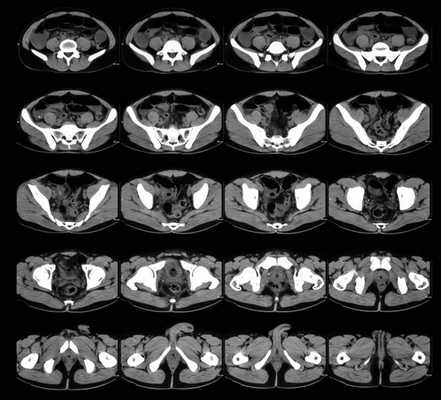

Органы малого таза (мужского) на томограммах (аксиальная проекция)

Компьютерная томография является одним из наиболее информативных способов сканирования. Внутренние структуры частично поглощают рентгеновские лучи, что дает возможность получить данные о плотности и однородности сканируемых анатомических образований. В результате диагностической процедуры аппарат выдает серию послойных фотографий, выполненных на заданной глубине. Ширина шага томографа начинается от 1 мм.

Сканирование проводят в аксиальной плоскости. С помощью компьютерной программы врач достраивает фронтальную и сагиттальную проекции. Для уточнения локализации, размеров пораженного участка и определения взаимного расположения анатомических структур реконструируют трехмерное изображение изучаемой области.